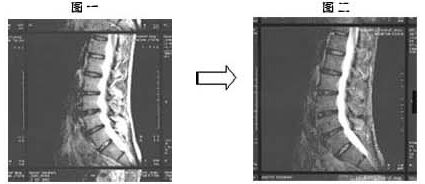

症状としては、一年程前に突然の腰痛で動けなくなり、整形外科を受診した結果、腰部椎間板ヘルニアと診断を受ける。診断後、牽引治療、抗炎症剤投与等の治療を受けるも効果はみず、これまで勤務していた自動車工場での勤務を断念し、一年間の休職に入る。その後、2003年の 3月に当院を受診、MRI【図1参照】で椎間板ヘルニアと診断。これまでの治療経緯を確認した上で、患者本人の合意を得て、バイオシャーク粉末 7.5g/1日での治療を開始した。

初診時の2003年 3月のMRI【図1参照】と2004年 4年のMRI【図2参照】を比較すると、椎間板の間の軟骨の回復がはっきりと見られ、ヘルニアの所見は改善したと診断できます。

椎間板の場合は、軟骨の再生という表現は適切ではないですが、軟骨が正常な弾力を取り戻したと考えられます。また、一ヶ月、二ヶ月後と痛みが減少し、消失している事からもヘルニアの症状に対しても、鎮痛効果があると考えられます。

约一年前因突然腰关节痛和坐骨神经痛导致无法行动,在整型外科诊断出罹患腰椎间盘突出症。之后,接受牵引治疗,服用抗炎药物等治疗方法,但始终未见成效。在那样情况下,该病患只好放弃汽车工厂的工作,办理停职一年。之后,2003年3月到本院接受诊疗,利用MRI(核磁共振图)(参看图一)诊断出腰椎间盘突出症。在确认该病患之前所接受的治疗经过后,得到患者本人同意,开始改以每日服用7.5g 百傲鲨锯峰齿鲛软骨粉末的治疗方式。

2003年3月初诊时的MRI(核磁共振图)(参看图一)与2004年4月的MRI(核磁共振图)(参看图二)相比,可清楚看到腰椎间盘突出症状,已有明显的改善。

椎间盘的场合,用软骨再生来表达不太合适,但可知软骨已恢复了正常弹性。而且,服用一个月后腰关节痛和坐骨神经痛感减少,两个月后疼痛状况完全消失,由此可得知百傲鲨对腰椎间盘突出症,具有消除坐骨神经痛和腰腿关节痛的效果。